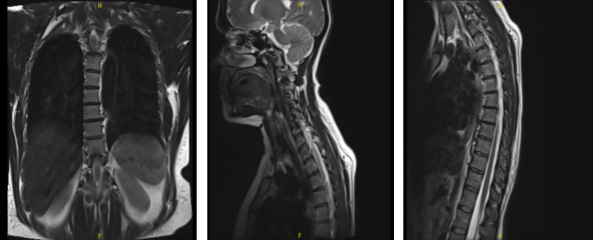

MRI-3T Thoracic Spine non-contrast

Osseous structures: Alignment of the thoracic spine is anatomic. There are no compression deformities. The bone marrow signal is overall age-appropriate. Paraspinal soft tissues: The visualized paraspinal soft tissues are grossly unremarkable.

Intervertebral discs: A left paramedian disc herniations present at T6-T7 level impinging on exiting left C7 nerve roots, causing mild spinal canal stenosis. No spinal canal stenosis is present. The neural foramina are patented.

Spinal cord: No areas of focal signal abnormality are present in the thoracic spinal cord. The conus medullaris terminates at the T12 level and is within normal limits. The left paramedian disc herniation at T6-T7 level causes mild mass effect on the existing left C7 nerve roots.